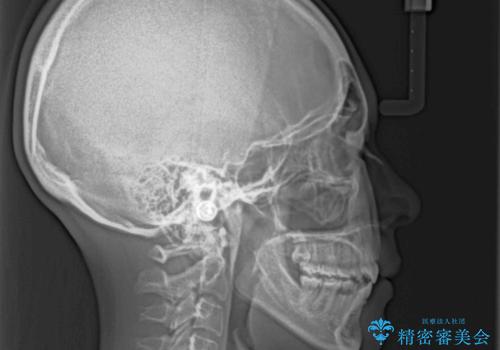

前に出ている上顎 抜歯矯正で唇を閉じやすく

- 口元の突出感と上下前歯のズレを気にして来院された患者様です。

舌の突出癖により上下の前歯は非接触であり、更には奥歯の咬み合わせが非対称となっている状態でした。

舌のトレーニングを行わないと上下前歯の接触達成は困難であるため、トレーニングをしっかりと行っていただきながら、治療を進めて行くこととしました。

通常は上下左右の第一小臼歯4本を抜歯することになりますが、右側臼歯部の咬合が上顎前突気味であったため、下顎右側のみ第二小臼歯を抜歯し、ワイヤー装置にて矯正治療を行うこととしました。

第二小臼歯抜歯はイレギュラーな治療手段であり、治療期間が延びる傾向にありますが、舌のトレーニングをしっかりと行ってくださり、2年弱という非常に短い期間で理想的な仕上がりを達成することができました。